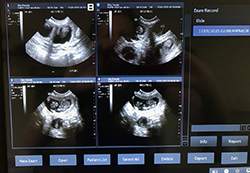

Mobile Ultrasound Pregnancy Scanning and Microchipping Services

Puppy Love scan and chip